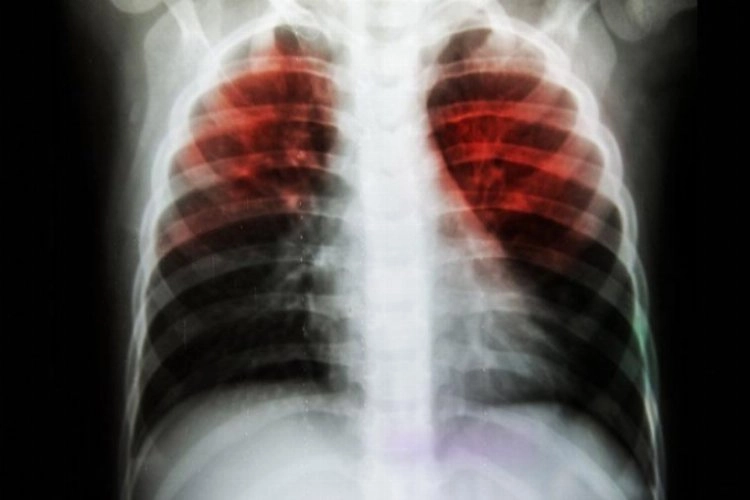

Malumunuz üzere verem (Tüberküloz) hastalığından bahsediyoruz.

Asırlar boyu milyonlarca insanın ölmesine sebep olan, insanlık tarihi kadar eski bir hastalık...

Verem, hava yoluyla, öksürmekle, hapşırmakla, konuşmakla bulaşan bir hastalık...

Ve verem, uzun süre havada canlı olarak asılı kalabilen mikropları soluduğumuz zaman önce akciğerlere, daha sonra kan yoluyla vücudun başka organlarına da yayılabilen bir hastalık...